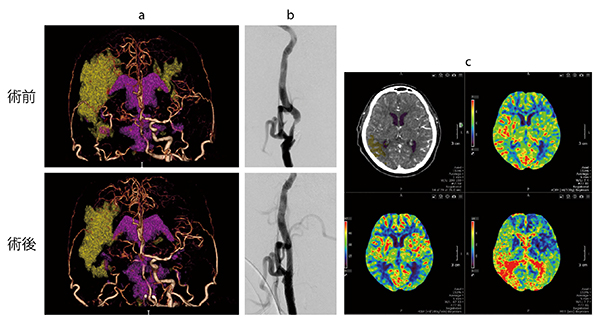

症例1 右内頸動脈閉塞、左頸動脈狭窄(perfusionによるCAS術前、術後評価)

術前:側副血行路があり血流は保たれているが血流遅延(ペナンブラ)領域あり

術後:左頸動脈ステント留置術(CAS)によってサマリーマップ(a)から血流が改善していることがわかる。また、perfusionマップ(c)にて術後の過灌流症候群(hyper perfusion)がないことを確認でき、早めに安静を解除できた。